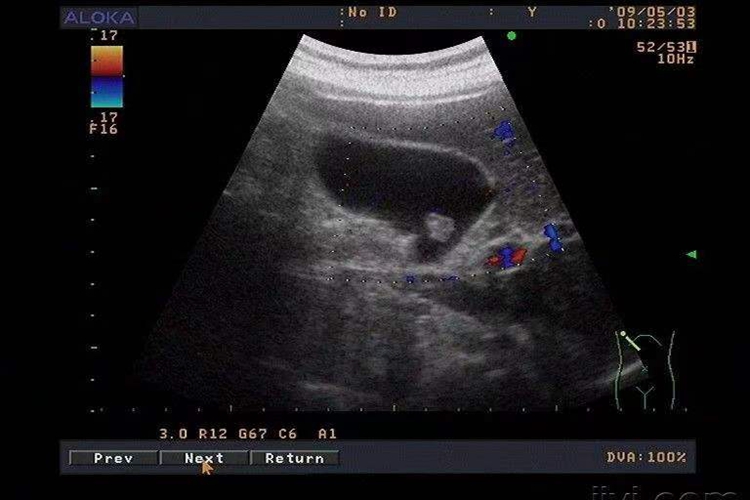

进行肝胆胰脾肾的彩超检查时,通常需要患者保持空腹状态。这一要求并非无的放矢,而是基于彩超检查的原理和人体生理特点的综合考虑。空腹的必要性通常包括胆囊充盈度、气体干扰等因素。

1、胆囊充盈度:在空腹状态下,胆囊内的胆汁会充分充盈,这使得胆囊的形态、大小以及内部是否存在结石、息肉等病变能够清晰地显示在彩超图像上。若患者在检查前进食,胆囊会收缩并排出胆汁,导致胆囊壁增厚、结构不清,从而影响对胆囊疾病的准确诊断。

2、气体干扰:进食后,胃肠道内会产生较多的气体和液体,这些气体会对超声波的穿透造成干扰,导致彩超图像的质量下降。特别是在检查肝脏、胰腺等器官时,气体干扰可能会掩盖病变,造成误诊或漏诊。